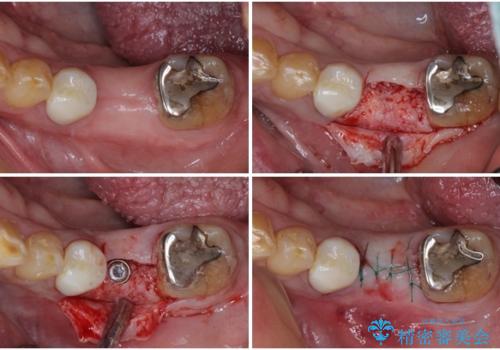

治療を開始したところ、上顎は排膿路が消失し、症状も落ち着きましたが、下顎は一向に改善されませんでした。

改めて診療を行ったところ、歯根破折が認められ、抜歯後にインプラント治療を行うこととしました。